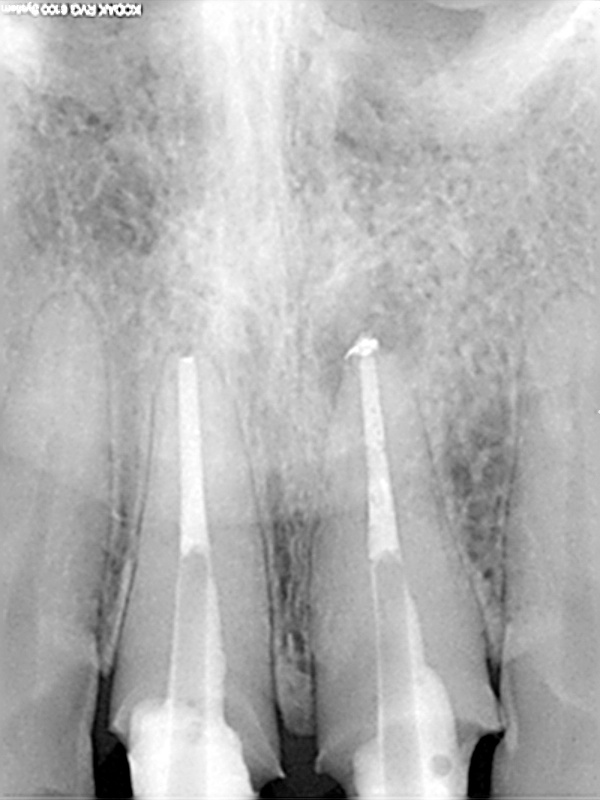

und wieder ein Recall

Abschlusskontrolle